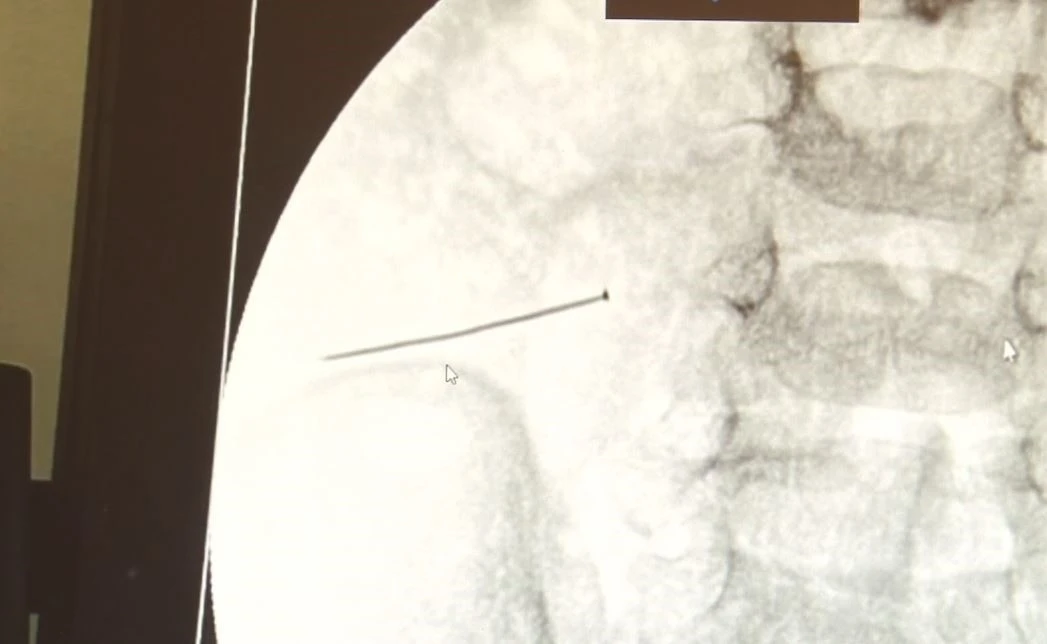

Öte yandan, yaklaşık 3 santimlik toplu iğne filme yansıyan görüntüsüyle gözler önüne serildi.

İstanbul’da 2 yaşındaki çocuk iddiaya göre toplu iğne yuttu sonrasında adeta karın ağrısıyla yerinde duramaz hale geldi. Babaanne, küçük çocuğun şikayetleri üzerine Şehit Prof. Dr. İlhan Varank Sancaktepe Eğitim ve Araştırma Hastanesi’ne götürdü. Burada yapılan tetkiklerde 2 yaşındaki çocuğun ince bağırsağında yaklaşık 3 santimlik toplu iğne olduğu ve bağırsağı deldiği belirlendi. Görüntülemeler sonrası 30 Ekim akşamı Çocuk Cerrahisi Kliniği Eğitim ve İdari Sorumlusu Doç. Dr. Sefa Sağ ve ekibi hemen ameliyata girdi. Başarılı operasyonla iğne olduğu noktadan alınırken aile de rahat bir nefes aldı. Doç. Dr. Sağ ise taburcu edilen hastasının durumuna ilişkin bilgi verirken yabancı cisim yutmalarına karşı ailelere önemli uyarılarda bulundu. "Yaklaşık 3 santim toplu iğnenin ince bağırsağı deldiğini, içeriğin karın içerisine dolduğunu gördük"